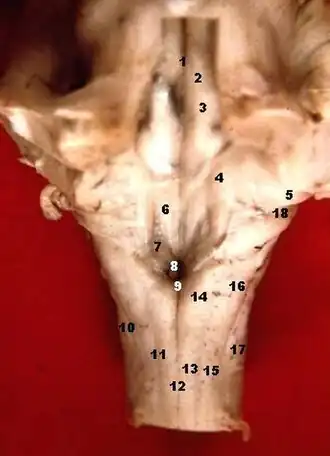

The rhomboid fossa is a rhombus-shaped depression that is the anterior part of the fourth ventricle. Its anterior wall, formed by the back of the pons and the medulla oblongata, constitutes the floor of the fourth ventricle.

It is covered by a thin layer of grey matter continuous with that of the spinal cord; superficial to this is a thin lamina of neuroglia which constitutes the ependyma of the ventricle and supports a layer of ciliated epithelium.

The fossa consists of three parts, superior, intermediate, and inferior:

- The superior part is triangular in shape and limited laterally by the superior cerebellar peduncle; its apex, directed upward, is continuous with the cerebral aqueduct; its base is represented by an imaginary line at the level of the upper ends of the superior foveae.

- The intermediate part extends from this level to that of the horizontal portions of the taeniae of the ventricle; it is narrow above where it is limited laterally by the middle peduncle, but widens below and is prolonged into the lateral recesses of the ventricle.

- The inferior part is triangular, and its downwardly directed apex, named the calamus scriptorius (as is shaped like a writing quill-nib)[1] is continuous with the central canal of the closed part of the medulla oblongata.

The sulcus limitans forms the lateral boundary of the medial eminence.

In the superior part of the rhomboid fossa it corresponds with the lateral limit of the fossa and presents a bluish-gray area, the locus coeruleus, which owes its color to an underlying patch of deeply pigmented nerve cells, termed the substantia ferruginea.

At the level of the facial colliculus the sulcus limitans widens into a flattened depression, the superior fovea, and in the inferior part of the fossa appears as a distinct dimple, the inferior fovea.

Lateral to the foveae is a rounded elevation named the area acustica, which extends into the lateral recess and there forms a feebly marked swelling, the tuberculum acusticum.

Winding around the inferior peduncle and crossing the area acustica and the medial eminence are a number of white strands, the striæ medullares, which form a portion of the cochlear division of the acoustic nerve and disappear into the median sulcus.

Below the inferior fovea, and between the hypoglossal trigone and the lower part of the area acustica is a triangular dark field, the vagal trigone, which corresponds to the sensory nucleus of the vagus and glossopharyngeal nerves.

The lower end of the vagal trigone is crossed by a narrow translucent ridge, the funiculus separans, and between this funiculus and the gracile nucleus, is a small tongue-shaped area, the area postrema.

On section it is seen that the funiculus separans is formed by a strip of thickened ependyma, and the area postrema by loose, highly vascular, neuroglial tissue containing nerve cells of moderate size.